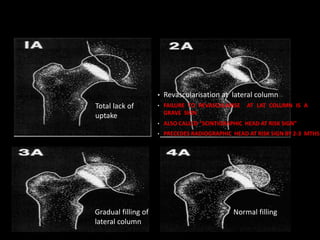

• Revascularisation at lateral column

• FAILURE TO REVASCULARISE AT LAT COLUMN IS A

GRAVE SIGN

• ALSO CALLED “SCINTIGRAPHIC HEAD AT RISK SIGN”

• PRECEDES RADIOGRAPHIC HEAD AT RISK SIGN BY 2-3 MTHS

Total lack of

uptake

Normal filling

Gradual filling of

lateral column